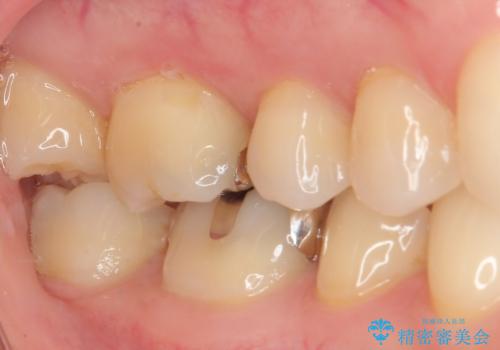

- 銀歯をやり替えたいとのことで来院された患者様です。金属の詰め物の大きさ、虫歯の範囲を考慮してセラミックの詰め物(セラミックインレー)で治療を行っていくことにしました。

拡大鏡視野下で、金属の詰め物(メタルインレー)、虫歯の除去を行い、セラミックインレーに適した形に整えました。